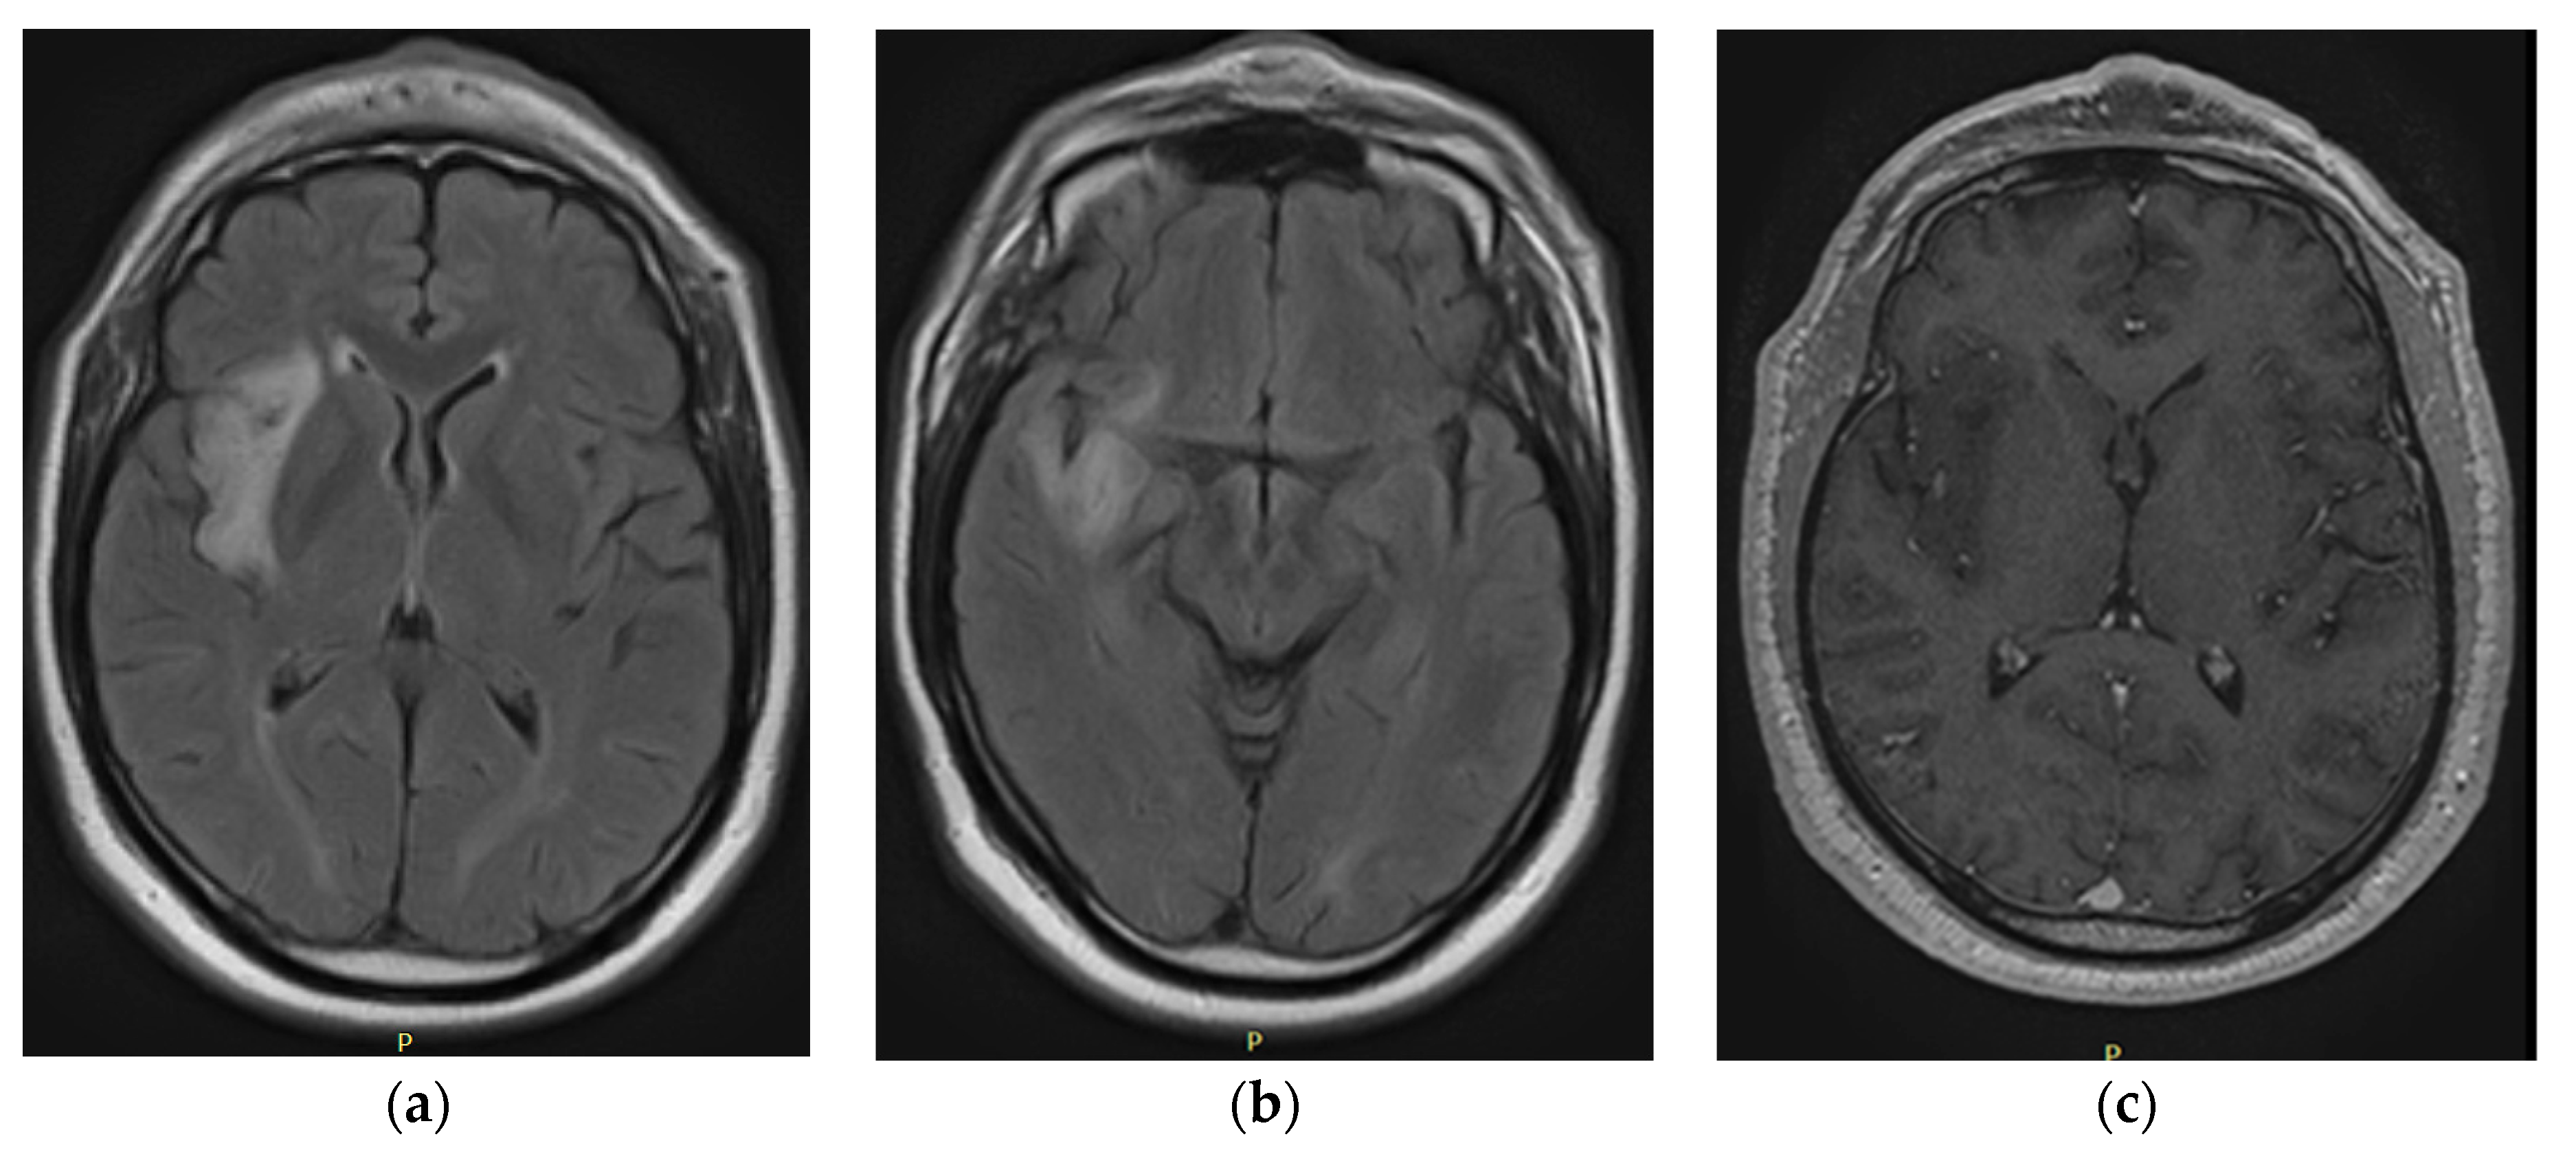

The initial paraclinical findings (Figure 1), such as magnetic resonance imaging of the brain that was performed in February 2020, were abnormal. An image with hyperintensity of the signal was found; it was oval, well defined, and hypocaptant, and it was located in the right periinsular territory with extension to the right temporal lobe. The lesion had a diameter of 4.4 × 1.5 cm and slight perilesional edema, with a compressive effect on the lenticular nucleus, as well as white matter with nonspecific signal hyperintensities associated with gliosis foci. No abnormal uptake of contrast agent was observed. The probable diagnosis was a nodular lesion in the perisylvian territory and right temporal area compatible with low-grade glioma.

Figure 1. February 2020: iRM FLAIR axial (a,b) and T1 gadolinium (c).